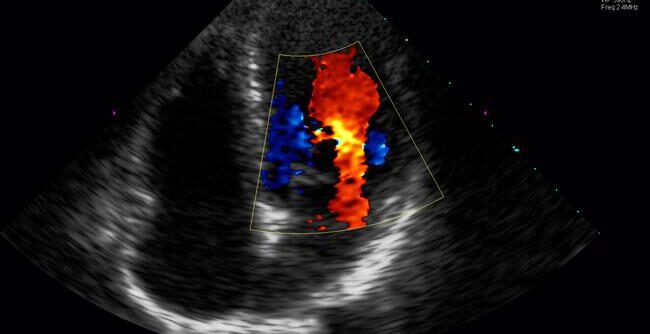

Absolwentka Wydziału Medycyny Weterynaryjnej Uniwersytetu Przyrodniczego w Lublinie.🎓 Szczególną pasją zawodową darzy kardiologię oraz ultrasonografię płuc i klatki piersiowej – to na nich skupia się jej codzienna praktyka kliniczna. 🫁♥️